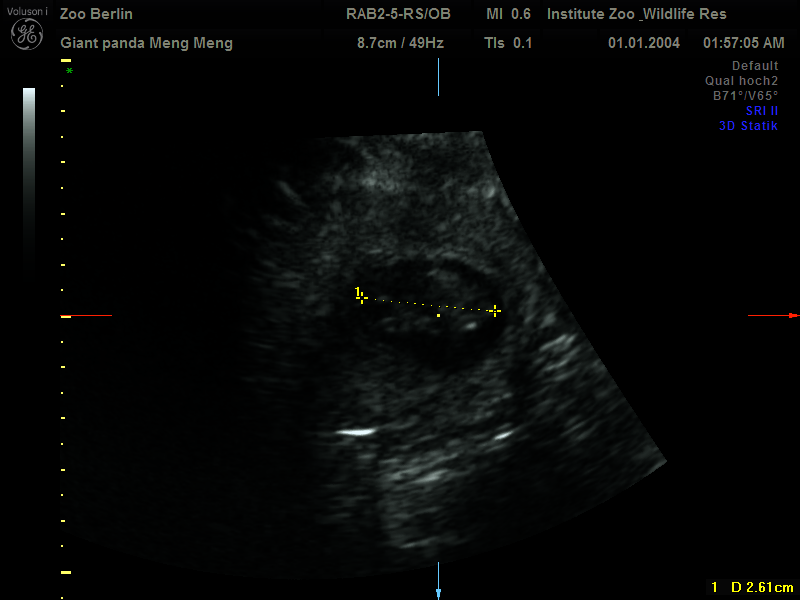

Certainty at last: after weeks of eager anticipation, a small rejoicing broke out on Sunday morning in Zoo Berlin's Panda Garden. First there was a heartbeat, then a second one was detected by the ultrasound machine. At seven o'clock in the morning, the "special panda unit" had gathered there for an audience with Meng Meng to try their luck again with the ultrasound of the recently uncooperative female panda. Just before the now well-coordinated team of keepers and veterinarians were about to finish their attempt around nine o'clock, the crucial images that everyone had been eagerly awaiting arrived. "A standing scan finally brought the happy news that Meng Meng was pregnant with two cubs. This was only possible thanks to the special bond of trust between humans and animals. Although she was visibly squirming in her belly, Meng Meng was persuaded to stand upright and accept the cool ultrasound gel and the ultrasound probe. The entire team was justifiably proud of this groundbreaking success," said a delighted Prof. Dr. Thomas Hildebrandt, Head of the Department of Reproduction Management at the Leibniz Institute for Zoo and Wildlife Research (IZW). "On Sunday, we were able to provide one of the earliest sonographic proofs of a giant panda pregnancy. The cubs are about 2.5 centimetres long and still need to grow properly before birth," he adds. The veterinarian is also considered an international expert on giant panda reproduction through his role as scientific advisor to the Chengdu Research Base. "The team's joy was great, especially since we had already had several unsuccessful ultrasound attempts," confirms zoo veterinarian Dr. Franziska Sutter, who also witnessed the examination, but adds: "Despite all the enthusiasm, we have to be aware that this is a very early stage of pregnancy and that so-called resorption - i.e. death - of the embryo is still possible at this point. We will continue to follow developments closely with ultrasound

examinations and hormone analysis. We very much hope that everything goes as well as it did last time in 2019."